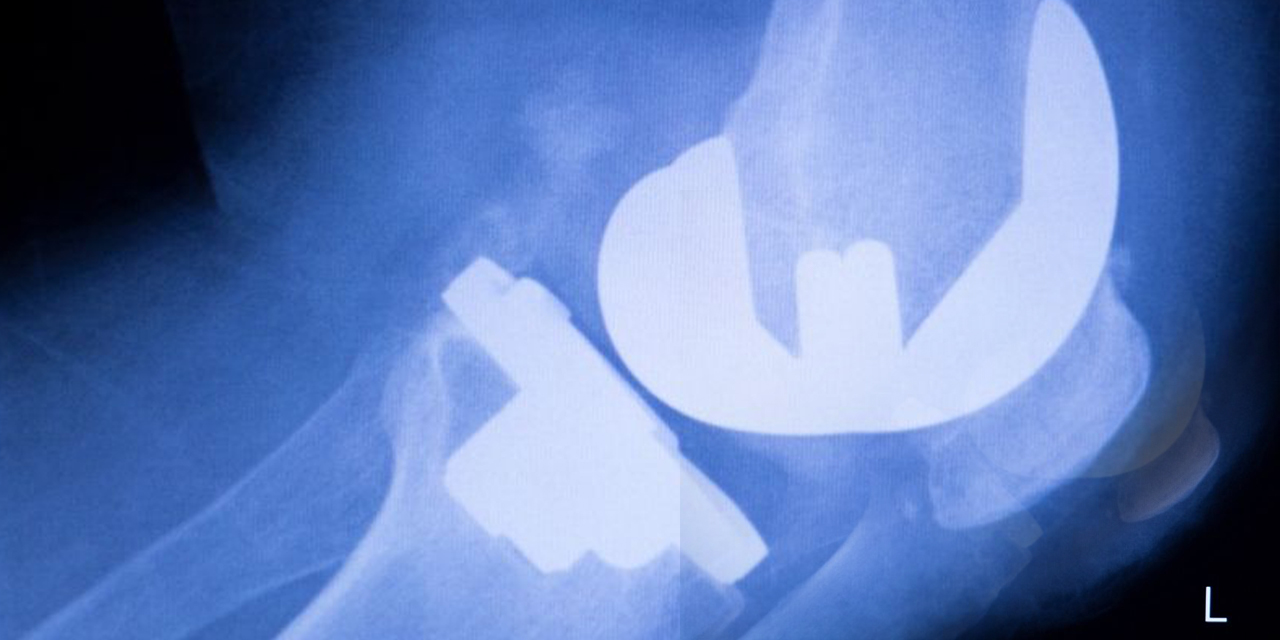

11 yıl sonra hayata sıfırdan başladı